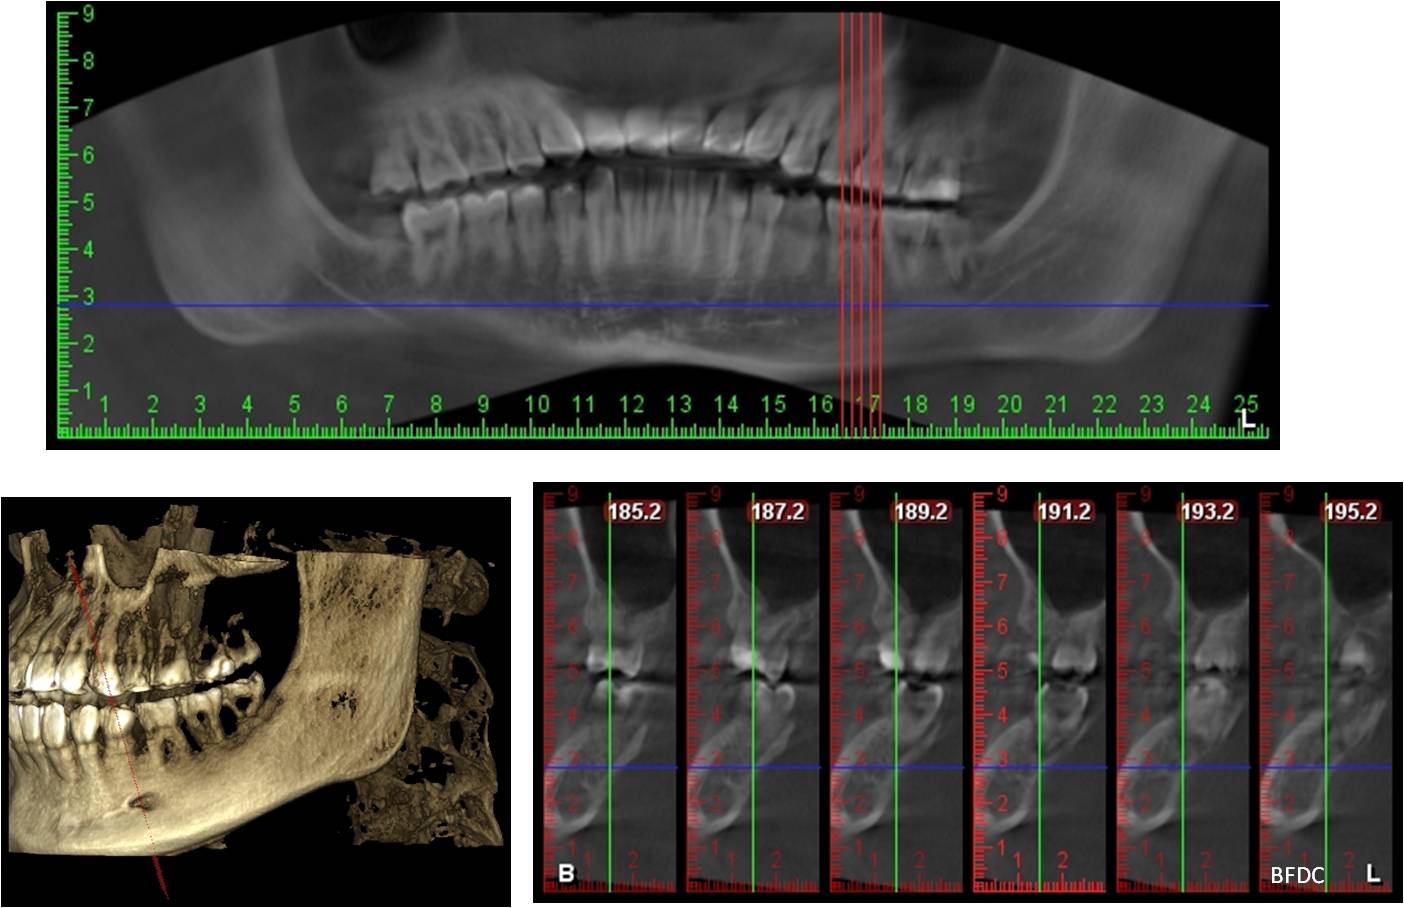

牙科專用的3D電腦斷層攝影;與傳統醫療電腦斷層相比較,輻射劑量只有一般電腦斷層的1/50;切片厚度一般醫療電腦斷層是2.0公厘,牙科3D電腦斷層則只有0.1公厘,就診當天馬上拍攝電腦斷層,馬上獲得立體影像。

電腦斷層顯示下齒槽神經距離遠